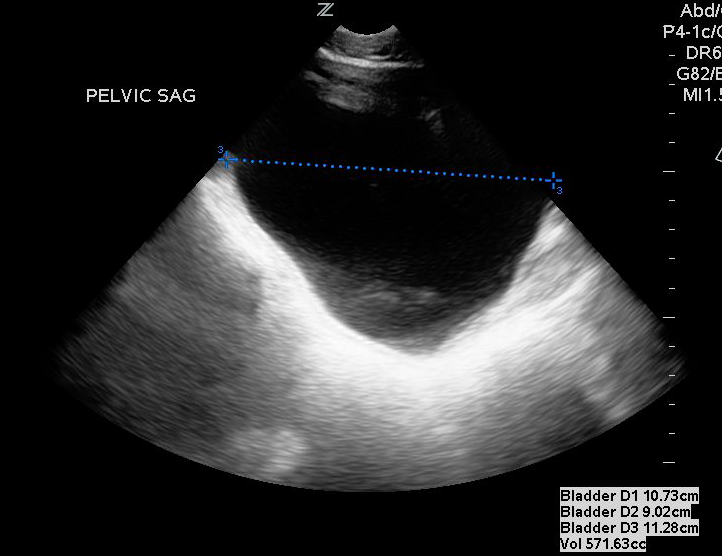

- For measuring bladder volume, use the US volume measurement feature or the formula 0.52 × Depth × Width × Height.

- In the transverse view, find the largest bladder size and measure both the vertical and horizontal length of the bladder image from inner wall to inner wall. This corresponds to the bladder depth and width, respectively.

- In the sagittal plane, measure the maximum horizontal length of the bladder image from inner wall to inner wall. This corresponds to the bladder height.

- Figures 3 and 4. Measurement of bladder volume in the transverse (Figure 3) and sagittal (Figure 4) views